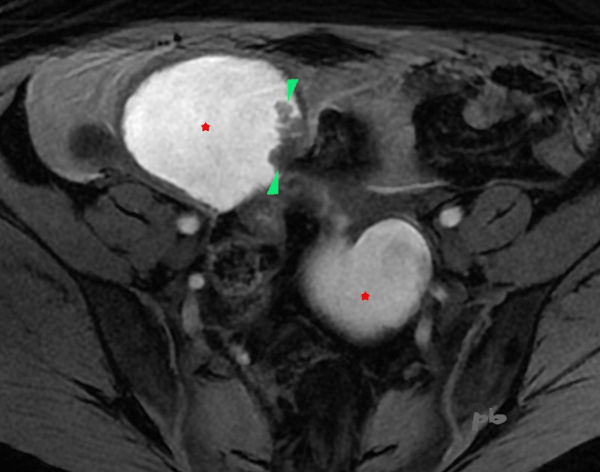

IRM axial T1 fatsat

Kyste endométriosique sur chaque ovaire (★) en hypersignal T1, contenant de petites images végétantes (►). Pas de prise de contraste après injection.

La patiente est opérée peu après : endométriose stade 4. Kystectomie ovarienne droite.

Diagnostic de kyste endométriosique confirmé en anapath.